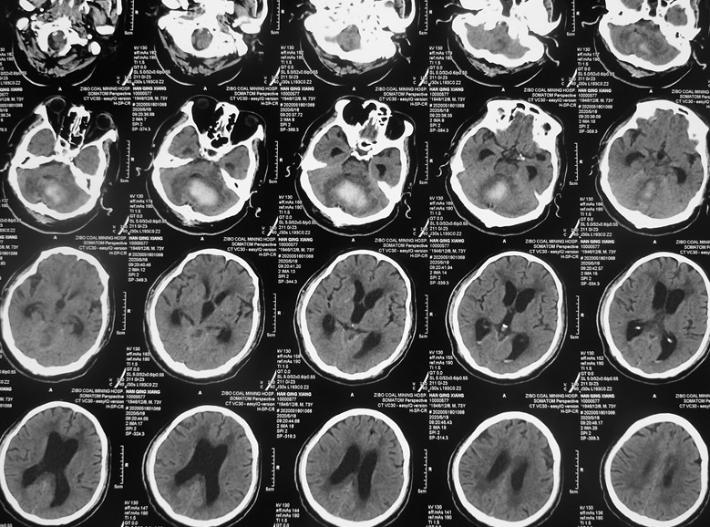

CT检查:小脑大量出血破入全脑室并梗阻性脑积水,脑干受压。

1周CT复查:脑室内积血有所吸收,但脑积水明显存在。患者昏迷状,瞳孔无明显变化。

半月CT复查:血肿明显吸收,脑积水有所改善。患者刺激可睁眼。

1月CT复查:血肿大部分吸收,脑积水缓解。患者可自行睁眼,有微弱意识反应,肢体肌力可达2到3级。